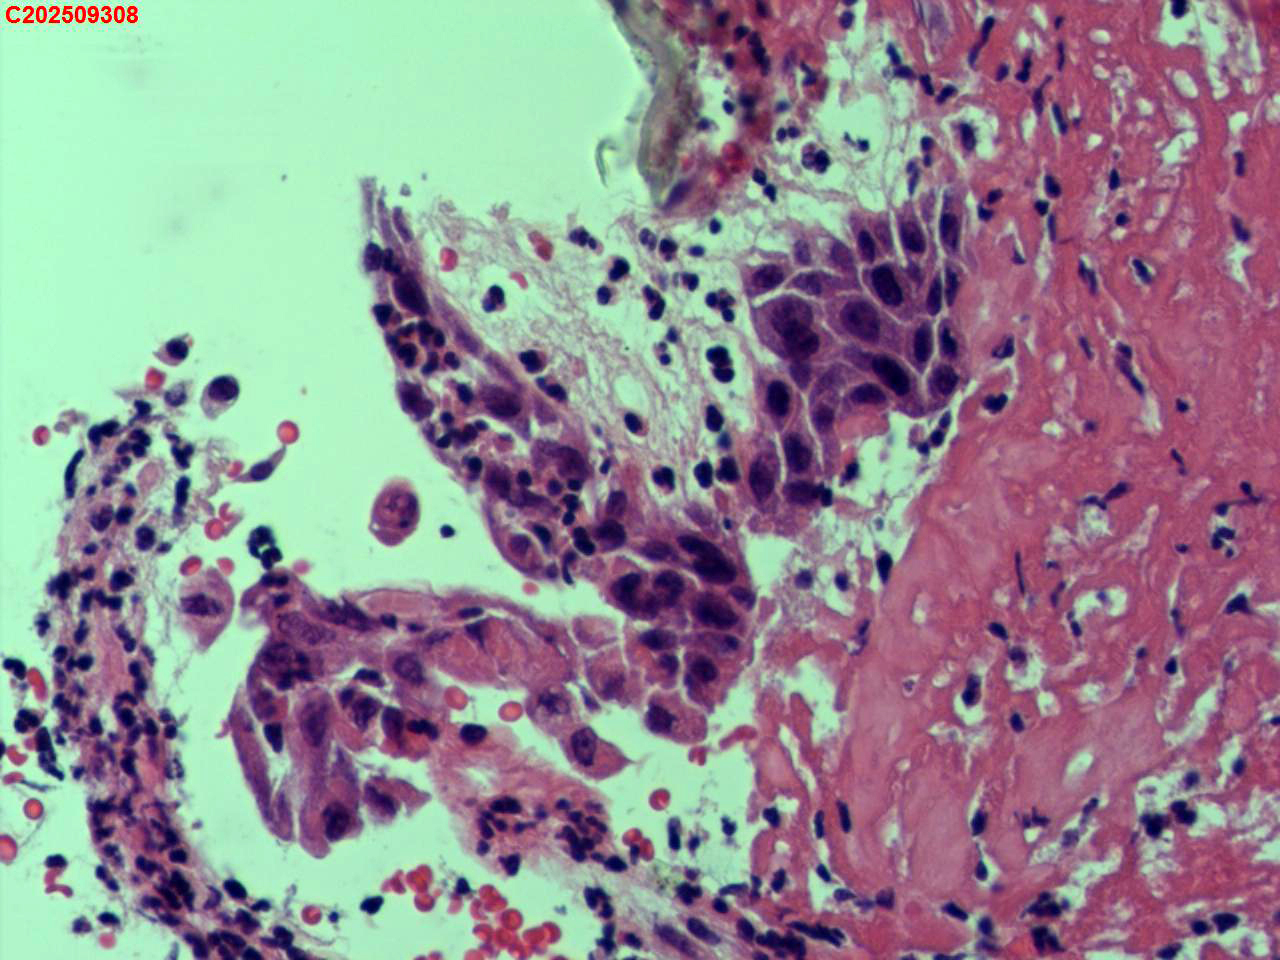

纤支镜咬检

肺结核、气管结核?

胸部CT:左肺多发病变及空洞考虑结核,请结合其他相关检查。右肺上叶小点状钙化灶。左肺门增大。

纤支镜:肉芽增生

送检粘膜鳞状上皮增生伴炎性渗出物及坏死物,建议做抗酸染色排除结核